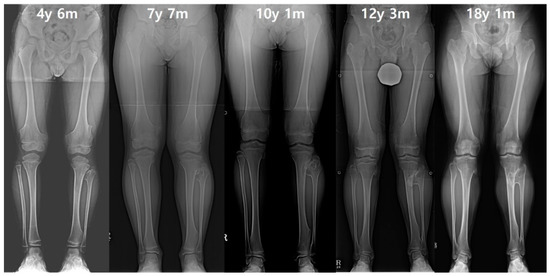

Figure 1. (A) The distance of proximal epiphyses (D) and physes (d) between tibia and fibula. The distance of proximal epiphyses was defined as the gap between the parallel line past the apex of the proximal fibula and the parallel line past the center of the distance between the line across the apex of the tibial spine and the most bottom of the condyle. The distances of proximal physes was defined as the gap between the parallel line passing through the midpoint of the distance between the line across the top of physis; the line crossing the bottom of physis was set as the reference line. (B) The measurement of the ankle joint. The tibiotalar angle was defined as the extension line of the tibial anatomical axis and a line perpendicular to the extension line that touches the dome of the talus. The left lower extremity indicated by the white arrow demonstrates a decreased distal tibiofibular distance compared to the right side, and a prominent ankle valgus deformity is also observed. (C) The tibiofibular synostosis. The white arrow indicates a definite bridge of an exostosis lesion connecting the proximal fibula and tibia without the overlapping cortex.